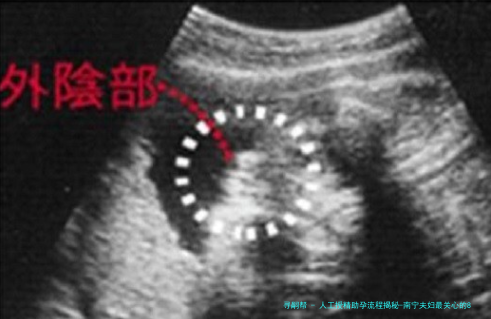

术前检查费(约2000-3000元):夫妇双方需要进行全面的身体检查,女性检查囊括妇科超声、内分泌激素测定等,男性便要进行精液常规解析等,以确保体质状况适合进行人工授精。